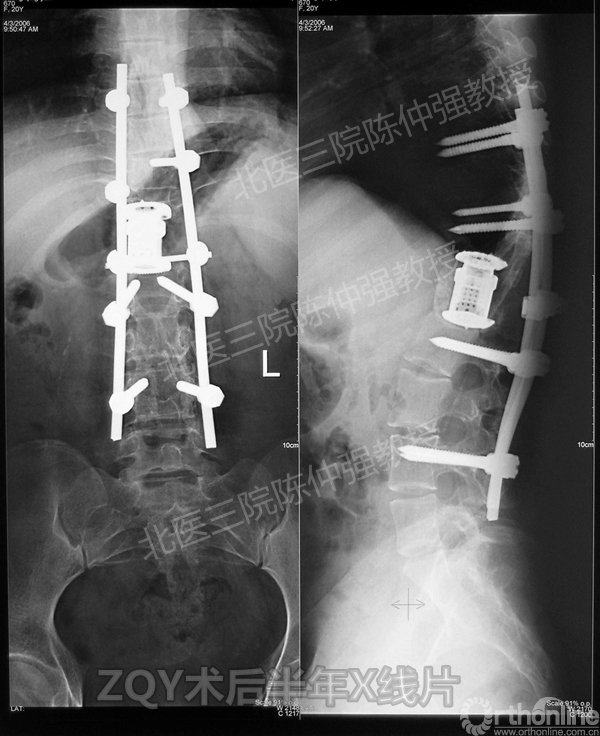

2005年,陈仲强教授在AOSpine年会上分享了一例胸腰椎陈旧结核性侧后凸畸形病例。资料如下:

ZQY术后半年

患者女性17岁,胸腰椎陈旧结核性侧后凸畸形,局部呈“麻花状”扭转,无神经功能受损表现。2005年,陈仲强教授带领团队实施后路+侧前方联合入路脊柱节段切除、双轴旋转矫形术。术后患者外观显著改善,神经功能正常。术后随访证实患者截骨矫形节段骨性融合良好,矫形效果持续良好。